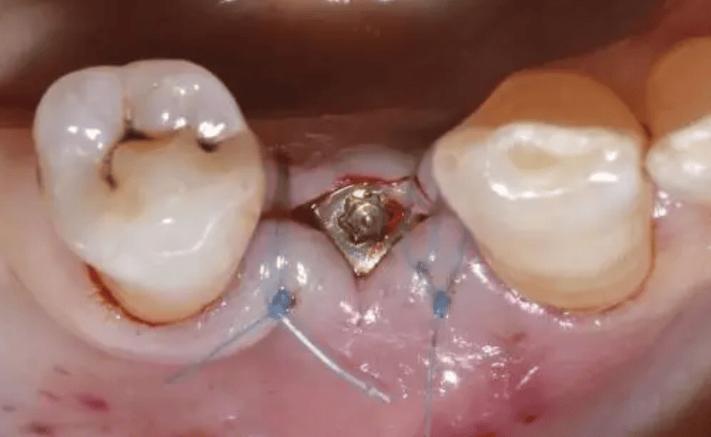

拆线操作通常在门诊进行,过程简单快捷,无需麻醉(因伤口已愈合,神经敏感度降低),医生会用镊子轻轻夹住线头,将缝线从伤口中缓慢抽出,部分患者可能感到轻微牵拉感,但一般无明显疼痛,整个操作约5-10分钟,拆线后医生会检查伤口愈合情况,确认无异常即可结束。